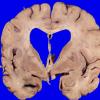

11B1 Pick Dz & ADNC (Case 11)_1

11B2 Pick Dz & ADNC (Case 11)_2

11B3 Pick Dz & ADNC (Case 11)_3

11B4 Pick Dz & ADNC (Case 11)_4

11B5 Pick Dz & ADNC (Case 11)_5

11B6 Pick Dz & ADNC (Case 11)_7

11B7 Pick Dz & ADNC (Case 11)_9

11B8 Pick Dz & ADNC (Case 11)_14